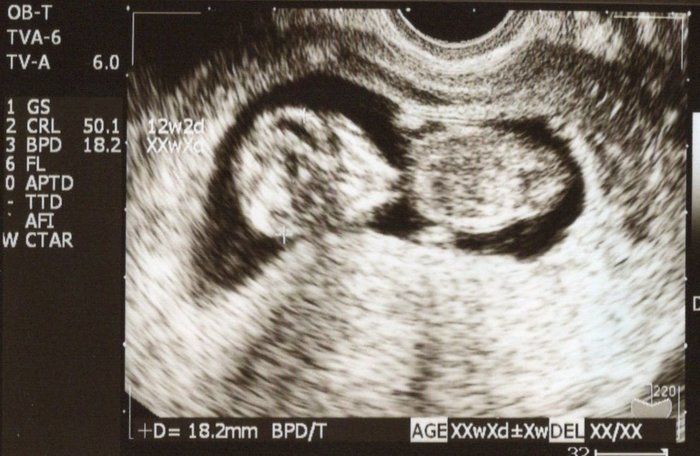

Tomomiさんの妊娠10週目のエコー写真 2頭身になった

順調に大きくなってくれて、平均より1週分程大きめでした。自分の腰痛や足の付け根の痛みを相談するも、私の場合骨盤ベルトは、付け根の痛くない方を向いて眠るようアドバイスをされました。小さなマイナートラブルは、息子がすくすく成長している証。「一緒に頑張って乗り越えようね」という気持ちでママも頑張りました。